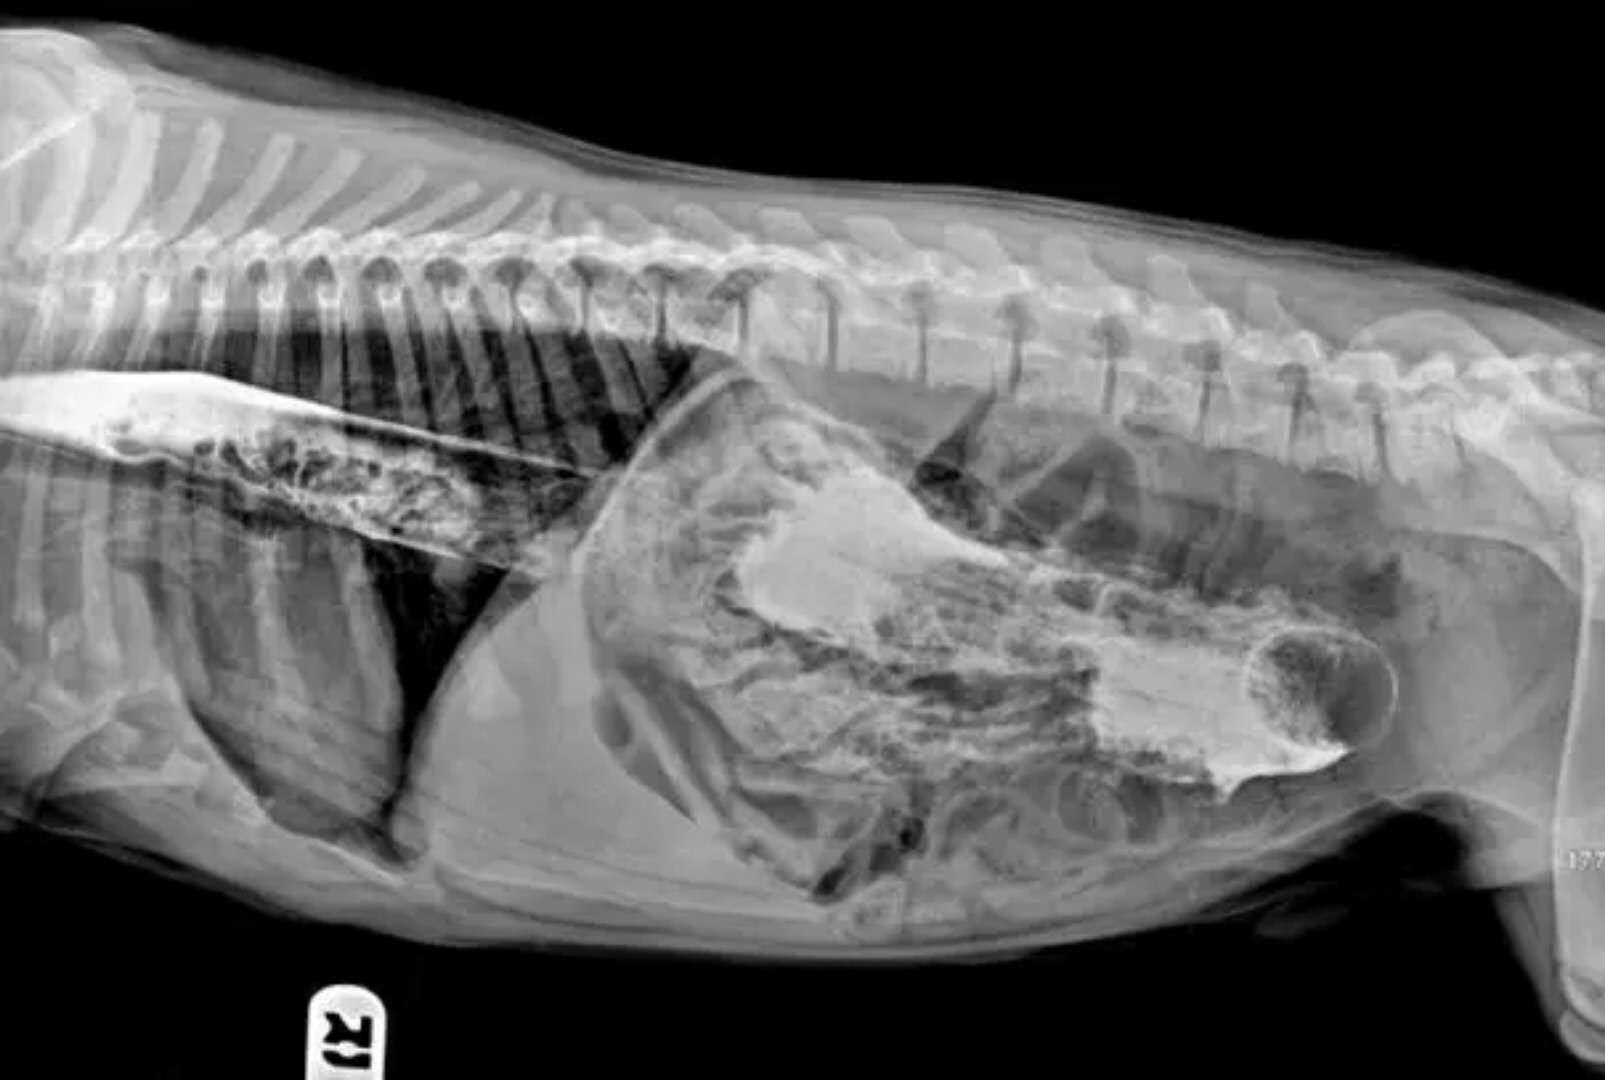

这是在狗狗胃里发现的勺子

这些都是在狗狗的胃里发现的,拍的X光图,看到那把刀在狗狗胃里,心里不紧张吗不担心 ,万一你家的狗狗也吃下去,想都不敢想!

狗狗似乎总是无法控制自己去吃一些没有营养价值的东西。针线、木勺、硬果壳、果核、塑料袋、珠宝、石块、抹布和袜子都有可能吃下去,狗狗胃内长期滞留这些异物不能被胃液消化,会造成胃黏膜损伤,影响胃功能。